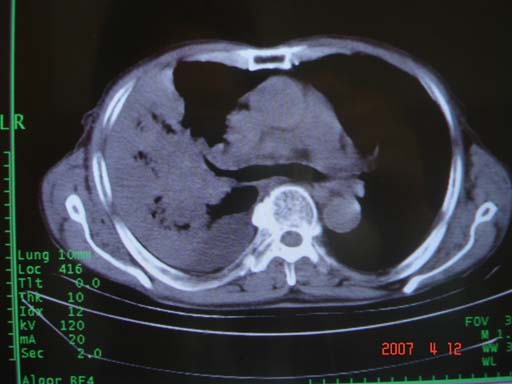

帮我 看看。男77岁咳嗽咯血2月发热2周!病人一般情况可 口痰为鲜红,有点象洗肉水(我看见他吐的痰了)

为何只有这么几幅图像?连纵隔窗都没有。但我发现上叶支气管显示不清,再加上年纪大,咯血等症状,恶性肿瘤首先得考虑。

考虑右肺新生物伴右中上肺阻塞性肺炎及含气不良,右侧胸腔积液。建议痰与纤支镜检查

考虑右侧中央型肺癌伴中上肺阻塞性肺炎、不张,胸腔积液。,建议支纤镜检查。

考虑:右上肺癌伴中上叶炎症,右侧胸腔积液。

病灶局限在右肺中上叶,呈大片状实变影,内见空气支气管征,支气管分支较柔软,纵隔内未见肿大淋巴结.支持:感染性病变_1 大叶性肺炎.2 干酪性肺炎.

优先考虑右上肺干酪性肺炎并同侧中叶播散、胸腔积液。分析:右膈肌未见升高、纵隔未见明显右移,胸部各组淋巴结未见可疑肿大,中叶可见支气管铸形,肺野、肺门未见可确定肿块。

右肺上叶后段支气管中断,首先考虑中央型肺癌并右肺不张及纵隔淋巴结转移,右侧胸腔积液。